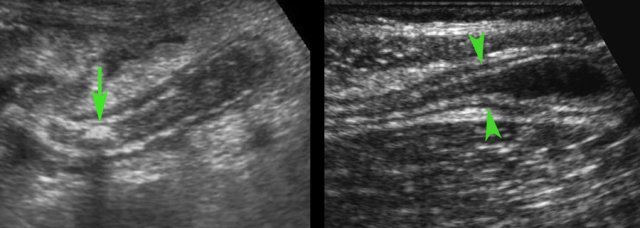

This US image shows an inflamed appendix in the axial (left) and longitudinal (right) view. This chapter on US for appendicitis is meant for all those actively involved in acute abdominal US.

- In 35 % of cases a fecolith (arrow) is found at the level of obstruction.

- In 65 % there is no apparent cause for a mechanical obstruction found (arrowheads).